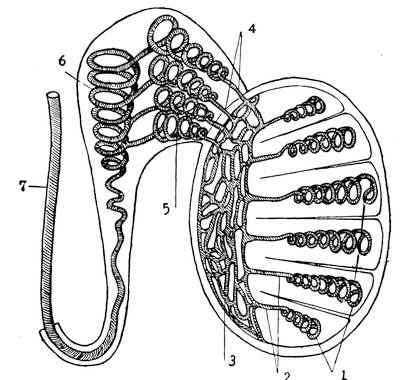

The male genitals, scrotum, testicles, descent of testicles, vas deferens, spermatic cord, seminal vesicles, ductus ejaculatorii, urethra, prostate, colliculus, sinus pocularis, penis.

Testicle.—The testicle is an ovoid organ with two surfaces, a median and lateral, with two poles, an upper and lower pole, and two margins, an anterior convex and a posterior straight margin. In the natural position, the upper pole is somewhat anteriorly inclined. The average weight of the testicle is 15 to 25 grammes, average length 5 centimeters, breadth 2 to 5 centimeters and thickness 3 centimeters. The superior pole and the posterior margin of the testicle are covered by the epididymis. The left testicle, as a rule, hangs deeper than the right.

Descent of testicles.—In embryonic life already, the testicle is connected, at its lower pole, with the bottom of the scrotal diverticle, the latter ventricle of the scrotum, by a cord containing unstriped muscular fibres, the so-called gubernaculum testis. This cord does not grow in length, hence, with the growth of the embryo, the testicle has to descend from its position, on either side of the mesentary along the spinal column. Thus, in the seventh month of embryonic life, each testicle descends through its respective inguinal canal into its compartment in the scrotum. In this descent the testicle takes along its peritoneal covering. When the bottom of the scrotum has been reached this peritoneal covering, together with the lining of the scrotum coalesce, and the two lamina form the above-mentioned tunica vaginalis propria.

Structure of testicles.—The testicle is covered with a thick, white, fibrous coat, the tunica albuginea. This tunica sends off about 200 to 400 septa or trabeculae testis. These trabeculae31 divide the parenchymatous tissue of the testicle into numerous conical lobules, and, converging towards the posterior margin of the testicle, form a solid fibrous mass, the so-called corpus Highmori.

The parenchymatous tissue of the testicles consists of numerous fine tubules, the canaliculi seminiferi. Each lobule contains a number of these fine tubules. In the beginning and through their entire course the seminal tubules or canaliculi are tortuous; towards their ends, however, they become straight. When they reach the corpus Highmori, the thickened, enlarged part of the tunica albuginea, they collect and unite, to form a network, the rete vasculosum. This rete sends off 12 to 14 large tubules, the vasa efferentia, which, running in a straight line, pass the corpus Highmori and enter the epididymis. The corpus Highmori serves as a point of entrance for the arteries and nerves and as an exit for the veins of the testicles.

Epididymis.—The epididymis is the excretory duct of the testicle. It is situated at the posterior margin of the same, covering this margin and the upper pole of the testicle. The upper32 end of the epididymis tapers off to pass into the vas deferens. The epididymis is divided into the head, middle piece and tail. At the lower point, the tail turns directly upwards and backwards, and is now called vas deferens. The vasa efferentia enter the epididymis at the head. The unfolded vas epididymis is about six meters long. Its diameter is about 0.5 millimeter. It gradually dilates as it approaches the vas deferens.